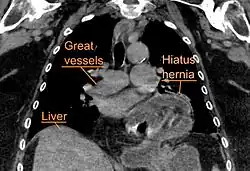

A hiatal hernia as seen on CT -

A large hiatal hernia as seen on CT imaging -